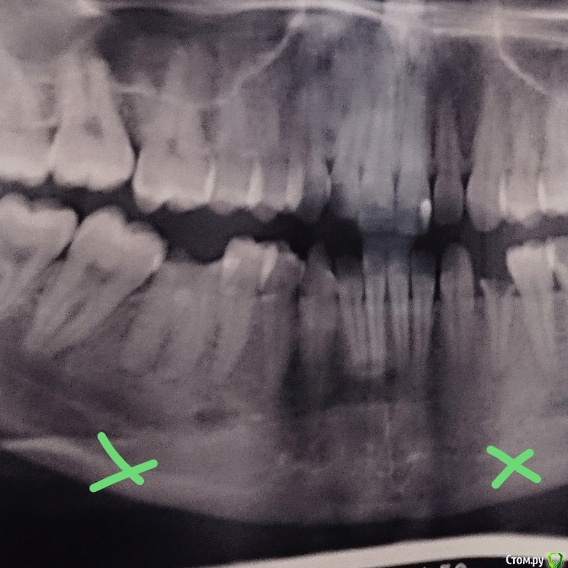

Mrs.guest Опубликовано 7 мая, 2016 Поделиться Опубликовано 7 мая, 2016 Добрый день, имеются два зуба, точнее то что от них осталось, один трехканальный разрушенный, ему уже больше 10 лет, второй одноканальный тоже под корень разрушен, ему больше 2х лет, оба не пролечены и жевательные , посетила двух врачей,один врач говорит что на трехканальный можно однозначно ставить коронку, а второй одноканальный нужно корень удалять, второй врач сказал, что можно ставить вкладку в корень и коронку на оба зуба но сначала оба зуба депульпировать . Я бы только рада, но переживаю как бы они оба потом не сломались или не испортились под коронкой и культевой вкладкой, т.к эти зубы давно в плохом состоянии и внутри них уже образовалась некая ткань, которая иногда кровоточит, мало ли на снимке это не видно. Не хотелось бы отдать около 35 тыс за оба зуба,, чтобы скоро удалять. Посоветуйте, сохранить оба зуба или только трехканальный или вообще стоит удалять оба и ставить импланты. Снимок прилагаю обоих зубов(отмечены крестиком) Второй вопрос о процессе, как это будет выглядеть, в первое посещение врач лечит каналы и ставит временную пломбу, во второе посещение делает слепки и временная все ещё стоит или уже делает вкладку? И на последней примерно через неделю ставят коронку? Сколько нужно посещений и времени. Спасибо за помощь Ссылка на комментарий